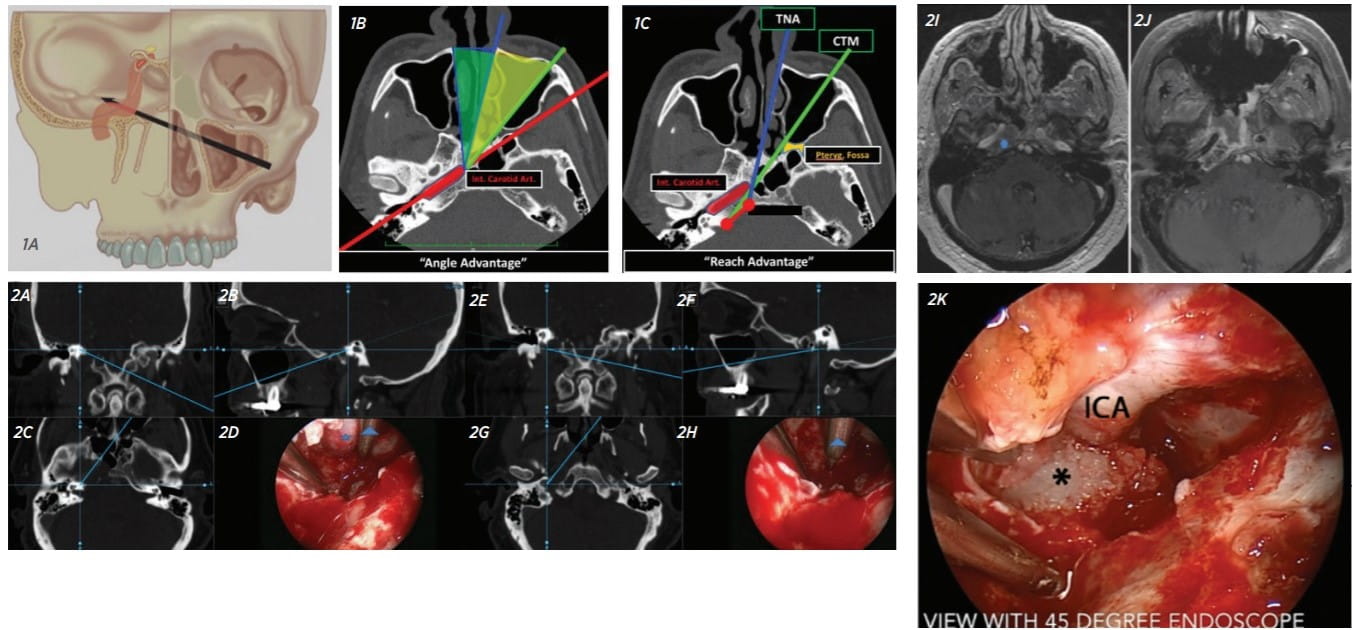

Figure 1. A: The CTM approach provides access to the contralateral PA. B: The CTM approach improves the angle of approach relative to the petrous ICA by 25 degrees. C: The CTM approach also provides a “reach advantage,” improving access to the PA.

Figure 2: Chondrosarcoma. A-D: Intraoperative navigation showing superolateral extent of dissection to IAC. E-H: Intraoperative navigation showing inferolateral extent of dissection to parapharyngeal ICA. I: Pre-treatment MRI. J: Posttreatment MRI showing total resection of a lesion. K: Intraoperative view of horizontal petrous segment of ICA with dissection of tumor (asterisk) at entrance of carotid canal (view is rotated 90 degrees).